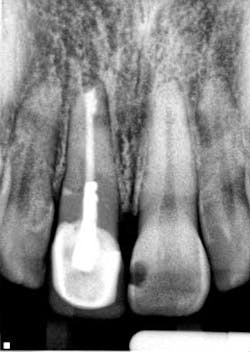

By Manish Garala, BDS, MSEndodontic surgery: an outdated clinical procedure?Endodontic surgery has developed the perception in some areas of dentistry as being an unpredictable and unnecessary procedure, especially with the advent of modern day implants. This opinion has been based on endodontic surgery being performed using outdated concepts and techniques that compromised the potential for clinical success, often resulting in the persistence of patient symptoms, periapical pathology, and, ultimately, extraction of the treated tooth (Fig. 1).

Fig. 1: Radiograph of a failing surgically treated endodontic case.The establishment of new surgical principles based on the use of enhanced magnification and illumination from the surgical operating microscope have addressed the technical and biological deficiencies that were previous barriers to successful, predictable surgical treatment.1The term microsurgical endodontics has now become synonymous with improved clinical success rates for endodontic surgical procedures, and scientific research has confirmed the merit of this procedure as more than just a last-ditch heroic attempt at tooth retention. Success rates of 90% and above have been reported from prospective case series and randomized controlled trials performed with contemporary techniques and protocols.2,3 The emphasis on using magnification for the identification of apical canal anatomy (Fig. 2), including additional canals, isthmuses, canal fins, and lateral canals (Fig. 3), apical disinfection of the root canal system, and the establishment of an impervious apical seal using biologically acceptable root filling materials such as MTA (Mineral Trioxide Aggregate, Dentsply Tulsa, OK) has enabled the routine achievement of these significantly improved success rates (Figs. 4 and 5).

Fig. 4: Endodontic surgery performed without adhering to contemporary microsurgical principles. An apical seal is not evident and apical pathology has developed radiographically with associated swelling and symptoms.